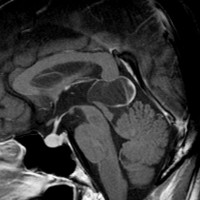

20歳くらいで発見され,40歳で腫瘍増大のために水頭症となりました。第3脳室開窓術で症状は消失,生検術では松果体細胞腫 WHO grade Iの診断です。さらに4年間観察したのが右側の画像です。ほとんど増大していません。わずかに変性性のう胞形成が前方に見られるだけです。